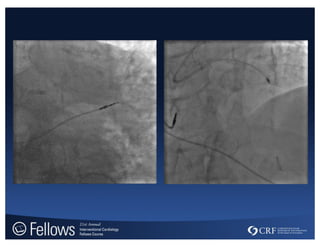

Guideliner Case

transradial-summit.org